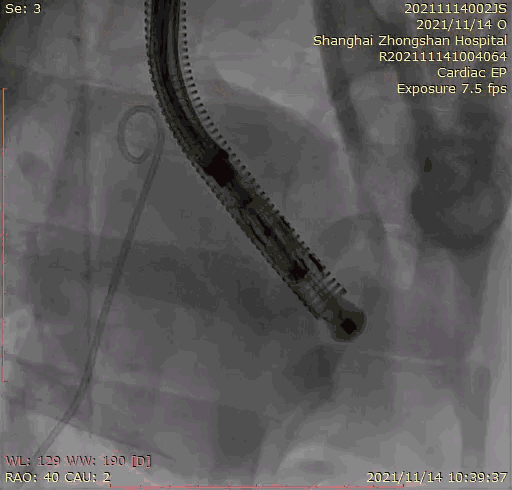

本次臨床前研究經(jīng)右側頸靜脈置入LuX-Valve Plus輸送系統(tǒng)可調彎鞘管,在DSA及超聲引導下將人工三尖瓣瓣膜植入到原有三尖瓣位置,利用獨特的錨定技術將人工瓣膜支架可靠固定在預定的位置。